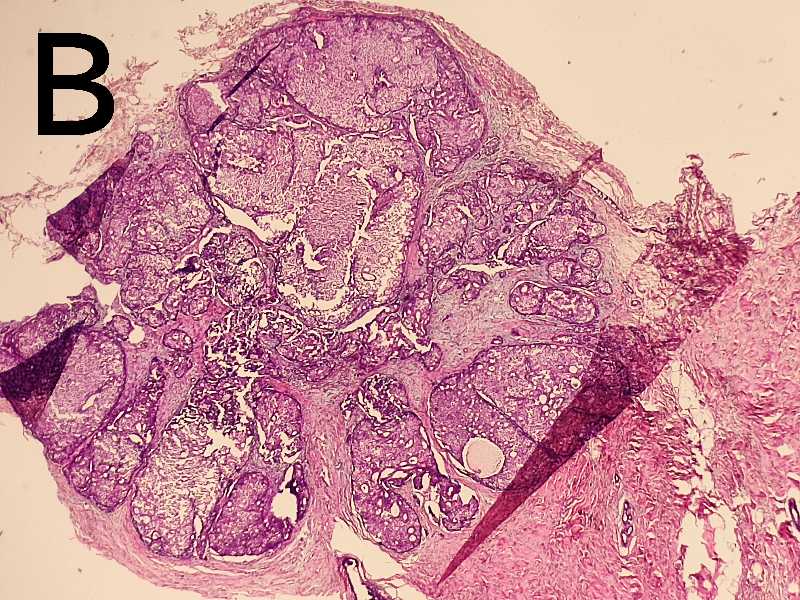

女62岁乳腺3个小结节,其中两个形态一致最大径分别3.5mm 5mm(A是导管内乳头状癌吗?);另一个结节直径4mm(B是浸润性导管癌还是浸润性实性乳头状癌?)